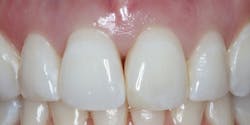

Results

I have found that most posterior teeth can be restored using a single shade. In cases where the tooth structure is very discolored, coupled with a shallow tooth preparation, I opt for an opaque layer beneath my core shade. For anterior cases, the enamel shades offer enough translucency to give the restoration a lifelike appearance. I tend to opt for a core shade to restore chipped incisal edges, and the results have been terrific. Nothing’s worse than a patient coming back with an anterior composite restoration that didn’t hold up; it leads to patients losing confidence in your skills, sometimes negative reviews, wasted chair time, and lost profitability. Polishing this composite is very efficient and effective, and so far, it’s maintained its shine. From my assistants’ perspectives, simplifying my systems made it easier to learn, maintain inventory, and prepare for direct restorations. From my perspective, simplifying composite restorations allows me to reduce chair time, minimize waste, and predictably and efficiently place restorations that my patients love.

G-ænial A’CHORD is a simplified-shade universal composite system that covers the 16 shades in the Classic VITA shade guide in five core shades. It’s indicated for all classes of composite restorations, including diastema closures and composite veneers. In instances where the restoration requires characterization due to translucency or for areas that require more opacity, enamel and opaque shades are available. This material attributes its excellent strength, wear resistance, gloss retention, stain resistance, and radiopacity to GC’s proprietary technologies: full-coverage silane coating (FCS) and high-performance pulverized CERASMART (HPC) fillers.